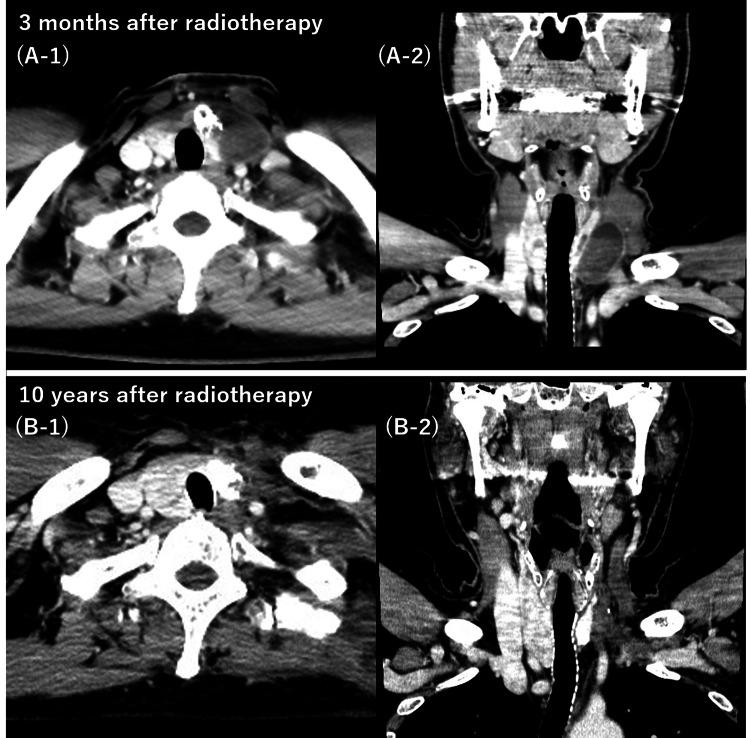

Anaplastic thyroid carcinoma, a rare type of primary thyroid cancer, is one of the most aggressive neoplasms with a poor prognosis. Many cases are in the advanced stage at the time of the initial visit, and curative treatment is impossible. Because of the highly radioresistant nature of anaplastic thyroid carcinoma, this condition cannot be properly controlled with conventional radiotherapy. Herein, we report the case of a patient with anaplastic thyroid carcinoma who underwent hypofractionated radiotherapy, attained a complete response, and is still alive more than 10 years after treatment with no evidence of disease. To overcome the high radioresistance of anaplastic thyroid carcinoma, we administered 50 Gy in 10 fractions three times a week. Furthermore, we administered paclitaxel and carboplatin sequentially before and after radiotherapy. Consequently, the patient completed treatment and reached a complete response. He is still alive more than 10 years after treatment with no evidence of disease or severe adverse events. Hypofractionated radiation therapy may provide good control of locally advanced anaplastic thyroid carcinoma.

间变性甲状腺癌是一种罕见的原发性甲状腺癌,是最具侵袭性的肿瘤之一,预后较差。许多病例在初诊时就已处于晚期,无法进行根治性治疗。由于间变性甲状腺癌具有高度放射抗性,传统放疗无法有效控制这种疾病。在此,我们报告一例间变性甲状腺癌患者,该患者接受了大分割放疗,获得了完全缓解,并且在治疗后存活超过10年,无疾病迹象。为克服间变性甲状腺癌的高放射抗性,我们每周三次,分10次给予50 Gy的剂量。此外,我们在放疗前后序贯给予紫杉醇和卡铂。结果,患者完成治疗并达到完全缓解。治疗后他存活超过10年,无疾病迹象或严重不良事件。大分割放射治疗可能对局部晚期间变性甲状腺癌有良好的控制效果。